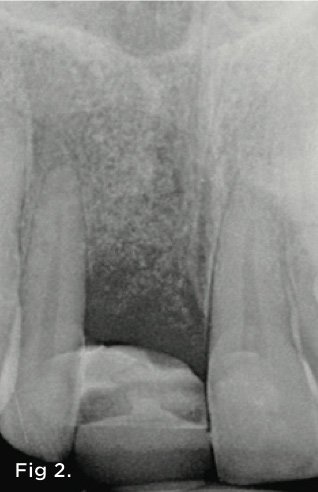

Fig 2. Radiograph showing the loss of periodontal attachment on the mesial aspect of tooth No. 7. A bone graft was placed when the implant was removed.

Figure 2

A 38-year-old Caucasian female patient presented with a high smile line and loss of the papilla between tooth No. 7 and edentulous adjacent site No. 8 (Figure 1). Understandably, the patient was unhappy and embarrassed about her esthetic condition. Her dental history revealed tooth replacement of No. 8 with an implant that eventually failed. The site had been previously bone grafted upon implant removal. She was given a composite pontic No. 8 bonded to a tooth No. 7 composite veneer as a transitional restoration. The implant was positioned too close to the proximal surface of tooth No. 7, which stripped the periodontal attachment of the root and ultimately caused loss of the papilla (Figure 2). As previously outlined, the treatment sequence would be to first provide a provisional restorative solution to evaluate the projected outcomes and assess if the patient was willing to undergo orthodontic therapy. In this situation, a full-coverage crown No. 7 with a cantilevered pontic No. 8, with artificial acrylic gingiva to replace the lost papilla on the mesial aspect of tooth No. 7 was used as a transitional temporary prosthesis (Figure 3). In addition, a composite resin restoration was placed on the mesial aspect of tooth No. 9 to restore its individual tooth proportion and shape. The patient’s esthetic outcome could now be evaluated with restorative correction alone; it was therefore mutually determined that the correction of her deformity would best be served with additional orthodontic forced eruption therapy. A fixed orthodontic appliance (brackets) was bonded to the teeth and temporary prosthesis. The level of the interproximal pink acrylic was used as a therapeutic guide for the amount of forced eruption required as well as the alignment of the mesial papilla of No. 7 to that of the adjacent papillae height (Figure 4). Floss was used to elevate the amount of vertical movement achieved relative to the adjacent papilla tooth No. 9. Eventually, all the artificial pink acrylic was removed. (Note that the distal papilla on tooth No. 7 also comes more incisal—in fact, it is slightly excessive at the endpoint of treatment [Figure 5]). However, the distal papilla and midfacial tissues of tooth No. 7 can be reshaped through clinical crown lengthening toward the end of treatment prior to definitive restoration, thereby restoring the proper papilla height-to-tooth ratio of 40%. After stabilization of tooth No. 7 for a minimum of 6 months post-orthodontics, an implant was placed in site No. 8. A papilla-sparing incision design was used for flap elevation (Figure 6), bone allograft was used to further augment the facial aspect of the ridge simultaneously with implant placement (Figure 7), and a resorbable membrane was used for guided bone regeneration.